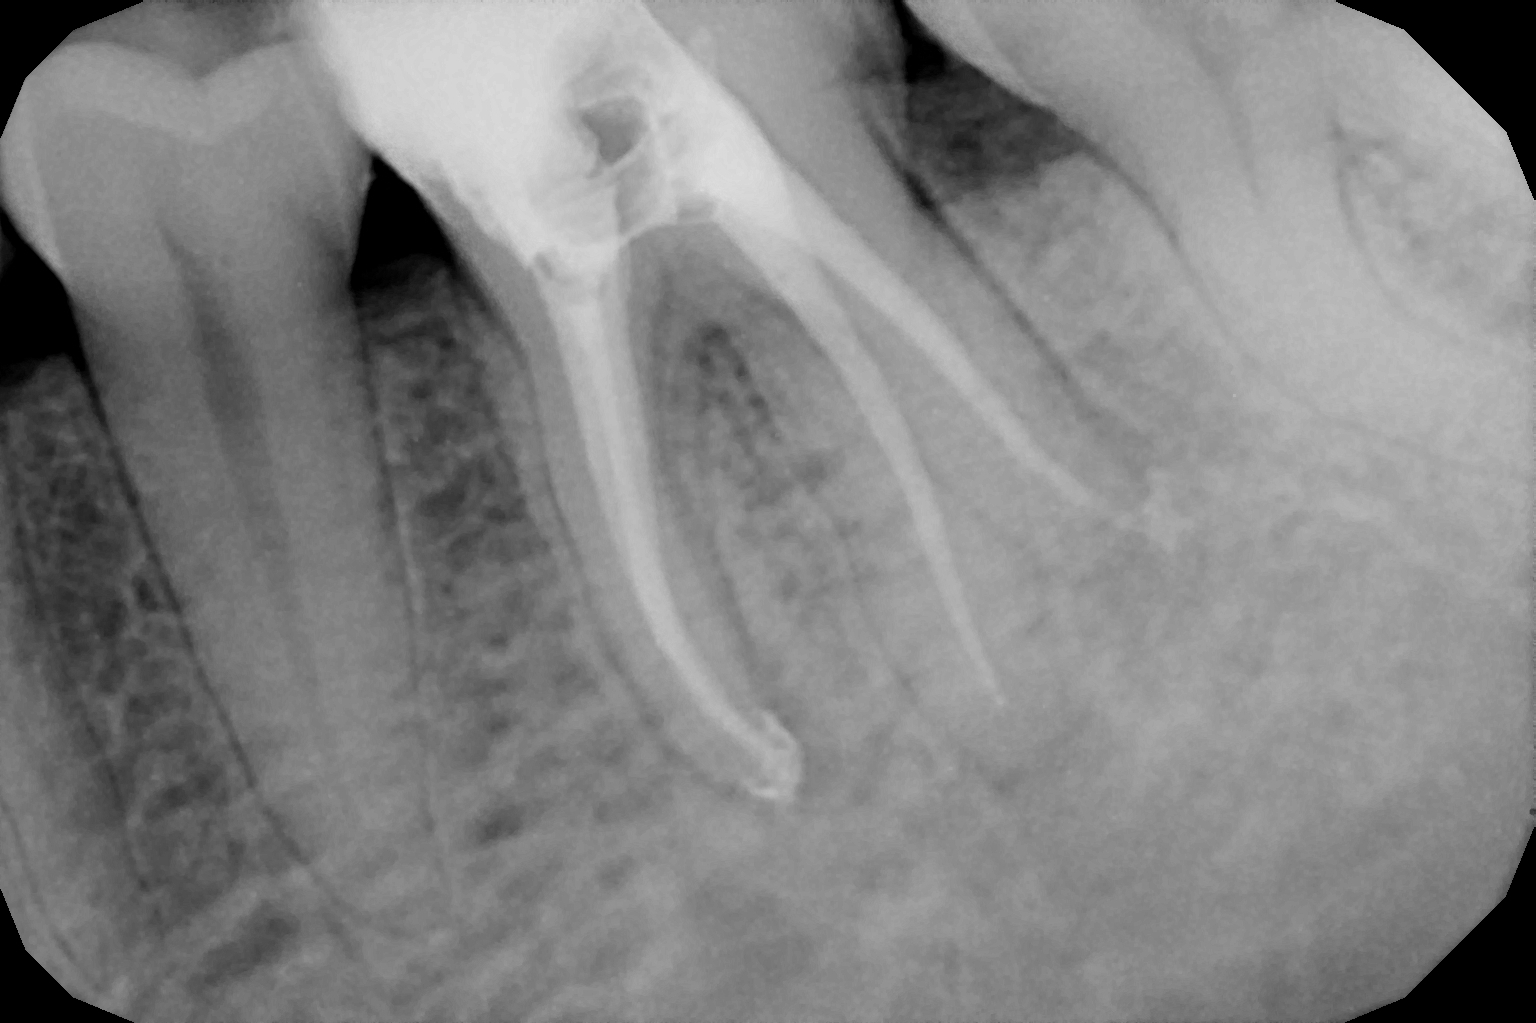

When the tooth is is sensitive to particularly hot and cold. When you cannot chew from that side or there is associated action of pain and swelling with same tooth, root canal treatment can save the tooth. For root canal treatment our clinic is equipped with state-of-the-art facility. We are following the protocol that is universally accepted and considered as a gold standard We are using rubber Dam for maximum possible cases. The root canal treatment is done under local anaesthesia that's why mostly it is painless . The rubber Dam isolation helps in proper irrigation and it provides much needed ease to the operating dental surgeon and the patient . The sealer and filling material are one of the Prime requisite of quality root canal treatment, it needs use of multiple X rays to really judge whether the results are acceptable or not. In older days root canal was just about cleaning the decade portion, removing the Pulp and filling it with biocompatible material but nowadays the root canal treatment it is very much advanced the precision is increased manifold. The materials and armamentarium that is required for efficient root canal have advanced in exclusion initial ways the the Abstract of all these things is the patients are getting great results after root canal treatment. Only the root canal is not sufficient to make a tooth functional again ,it needs use of Core buildup material and complete coverage Crowns according to the tooth position. During Covid19 time we have studied and implemented use of of high strength composites in our practice and the results of it are amazing many times it has saved tooth from being restored with crown. In some cases where the tooth is grossly carious we need a complete coverage crown. The materials and the Crown materials are are available in various price ranges. We prefer only the best of materials for our patients. We believe that to perform best treatment we need best of the armamentarium and best of the material for our patients who value and deserve the best of the treatment.